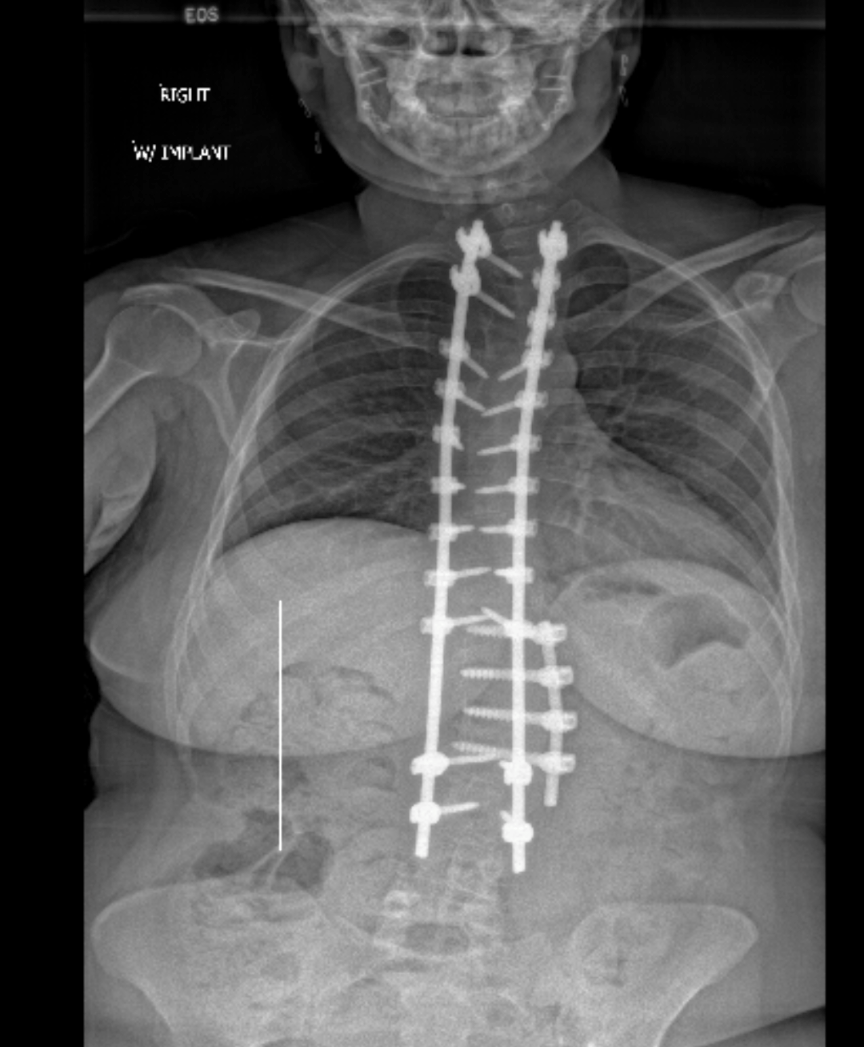

In March 2024, I underwent my second extensive spinal fusion from t2-l3 where unfortunately, my dominant arm became paralyzed. During recovery, I also developed rebound pulmonary emboli and some screws in my spine became misaligned from pushing myself too hard, too soon.

I've since healed from these surgeries and after meeting with my spine surgeon this week, we've made plans for a third, urgent revision spinal fusion for this upcoming October. I will have my existing fusion extended from t2-l3 to t2-l5 (or t2-pelvis) to address nerve injury in my lower spine under the existing hardware from degeneration related to my disease. The misaligned screws in the thoracolumbar region will be replaced and my two large paraspinal rods will also be removed and replaced with even longer ones.